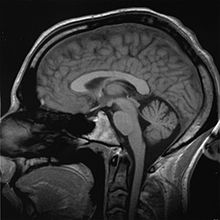

According to (Blomberg, 2011), the electric activity of human brain usually starts during the late prenatal period and it is believed that at birth all the neural cells are fully developed to full number. According to neurologists,the brain is divided into three parts which are the brain stem, cerebellum and the cerebrum. According to (Finger, 2001)

Picture of the human brain showing the cerebellum painted scarlet

the cerebrum has a layer on its surface called the cerebral cortex which remains by far the largest region of the central nervous system. It is said that “cerebrum has a number of regions for the expression of behavior and emotions, movement initiation, conscious awareness of sensation and complex analysis. The highest influence to encephalography comes from electric activity of cerebral cortex due to its surface ”position”. Encephalography directly measured from the cortical surface is referred to as (electrocortiogram). Scalp recordings of randomly neuronal activity in the human brain, electroencephalography (EEG), makes it possible for recording of potential changes within a period of time between a signal electrode and a reference electrode. ‘The electroencephalography (EEG) system is comprised of electrodes, amplifiers (with appropriate filters), and a recording device for recording band frequencies’. The scalp is prepared by removing the dead skin through a light abrasion minimizing resistance as a result of the dead cells of the skin A number of numerous small pieces of electrodes are then placed on the surface of the scalp and connected to the input of the amplifier. This is according to Teplan. (2002). in his book “FUNDAMENTALS OF EEG MEASUREMENT “. The voltage between the signal electrode and the reference electrode is then amplified. During the recording process, a number of activation procedures may be used. Procedures used include closure of the eyes, lack of sleep and sleepiness, alertness and being drowsy.Neurologists note that, ‘only large number of active neurons is capable of producing electrical activity that is recordable on the surface of the head’. Electroencephalography (EEG) is very sensitive to a large number of states including state of stress, sleep, and alertness. With varying administration of stimulus, a range of frequencies of neural activity are recorded[4] [5] .